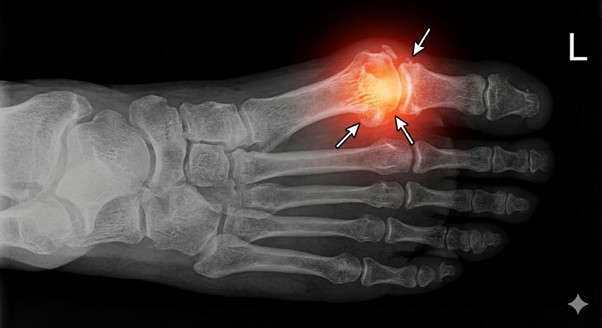

האם אתם מרגישים כאב חד בבסיס הבוהן הגדולה בכל פעם שהרגל "דוחפת" את הרצפה להליכה? אם הבוהן שלכם איבדה את הגמישות שלה ואתם סובלים מנוקשות (ולעיתים נפיחות מעל המפרק), כנראה מדובר בהלוקס ריגידוס (Hallux Rigidus) – שחיקה ניוונית של המפרק. במצב זה, מדרס רך "רגיל" לא יעזור, ולעיתים אף יחמיר את הכאב. אתם צריכים פתרון שימנע מהמפרק להתכופף.

- פיזור לחצים: הורדת העומס הממוקד מראש המפרק (Metatarsal Head) וחלוקתו על שאר כף הרגל.